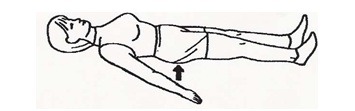

به پشت دراز بکشید و پاها را صاف کنید، مچ پاها را رو به بالا خم کنید و زانوها را محکم به پایین روی تخت فشار دهید. 5 ثانیه در این حالت بمانید، سپس 5 ثانیه استراحت کنید. این حرکت را 10 بار تکرار کنید.